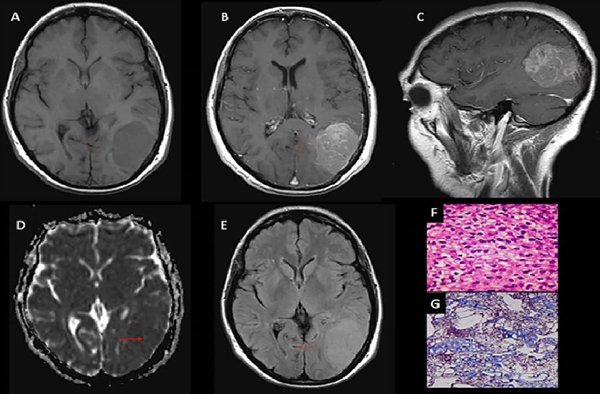

Los 3 grados histológicos (OMS) se categorizaron en 2 grupos: bajo grado (Grado I) y alto grado (Grados II y III) (Figuras 1, 2 y 3).

Figura 2. Meningioma de células claras, grado II OMS. (A) RM T1 axial: Meningioma parietooccipital izquierdo que produce efecto de masa (flecha). (B y C) T1 axial y sagital con Gd: Realce tenue heterogéneo (flechas). (D) Mapa de ADC: Comportamiento isointenso con aislados sectores de aumento de intensidad (flecha). (E) RM Flair axial: Efecto de masa, sin edema vasogénico (flecha). (F y G) Microscopía: Proliferación meningocelular con sectores de hipercelularidad y aumento de la tasa núcleo-citoplasma, con presencia de necrosis tumoral multifocal y sectores de atipia nuclear con nucléolos y 5 mitosis por 10 campos de aumento.